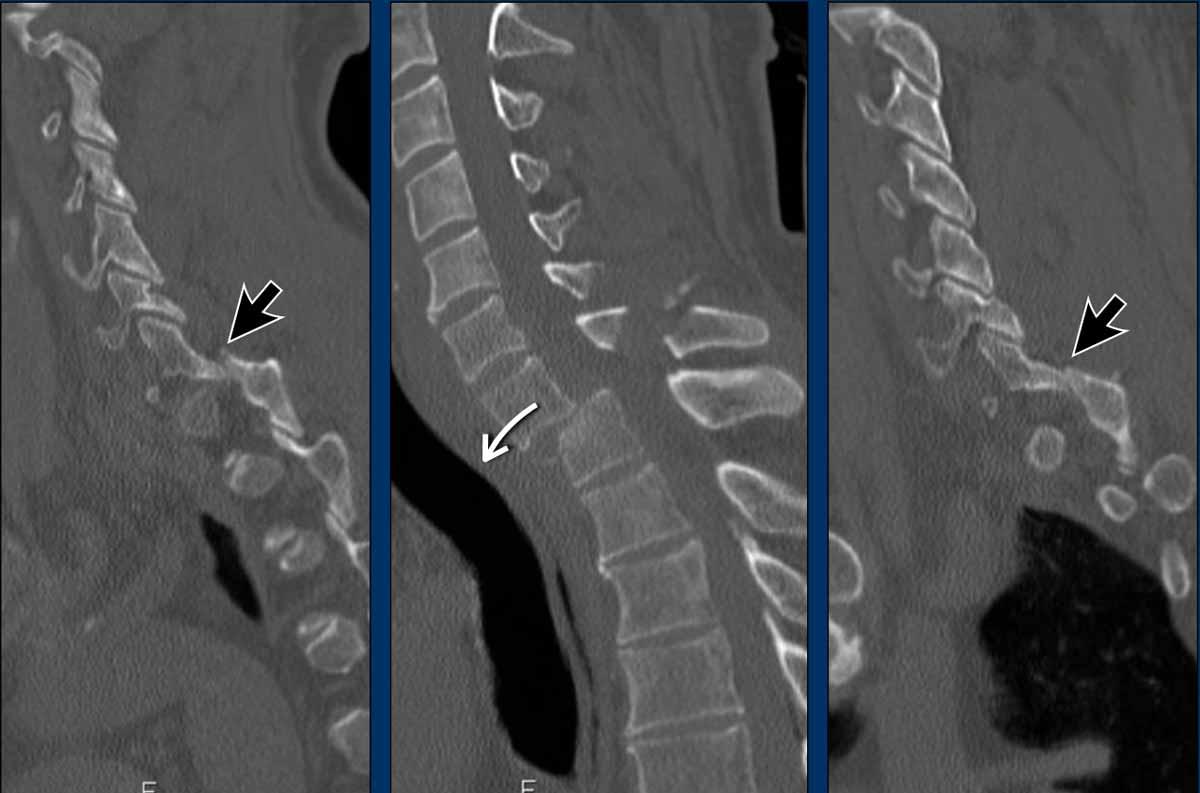

What are the findings?

What is the highest AO-type of injury?

Findings

- Dislocation of the proximal vertebrae anteriorly (white arrow).

- Both facet joints are perched (black arrows). Perched means to be situated above or on the edge of something. In this case the inferior process of vertebral articular joints appears to sit on the ipsilateral superior articular process of the vertebra below.

- Due to the anterior displacement a fracture of the spinous process is seen, in a horizontal oblique course.

Conclusion

Type C injury.